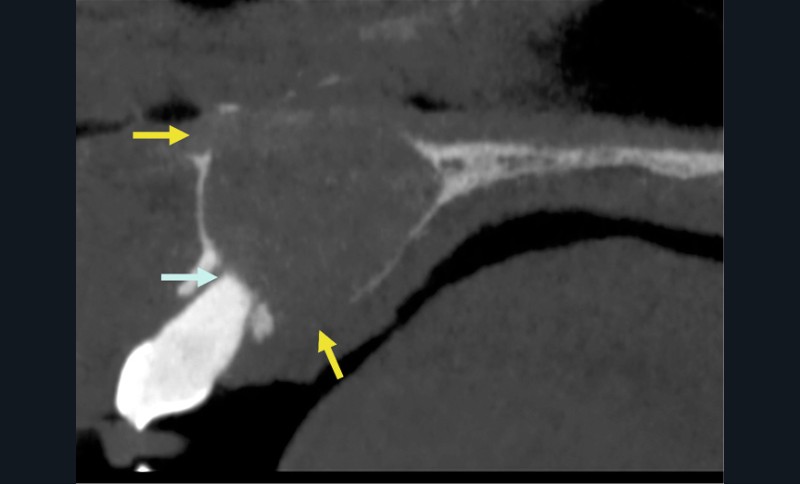

- Lorsque le kyste devient volumineux : possibilité de fenestrer la corticale palatine et/ou vestibulaire. Il peut également se développer dans les fosses nasales ou être associé à des résorptions radiculaires (moins de 25% des cas) (fig. 4).